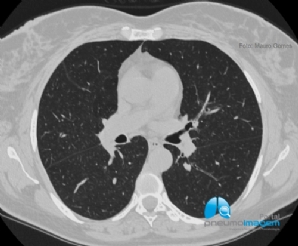

CASO CLÍNICO #46

Paciente tabagista, oligossintomático e cuja TCAR de tórax apresenta essas alterações. Qual o diagnóstico mais provável? Deixe os seus comentários abaixo. ***** A smoker, oligosymptomatic patient whose chest HRCT shows these changes. What is the most likely ...